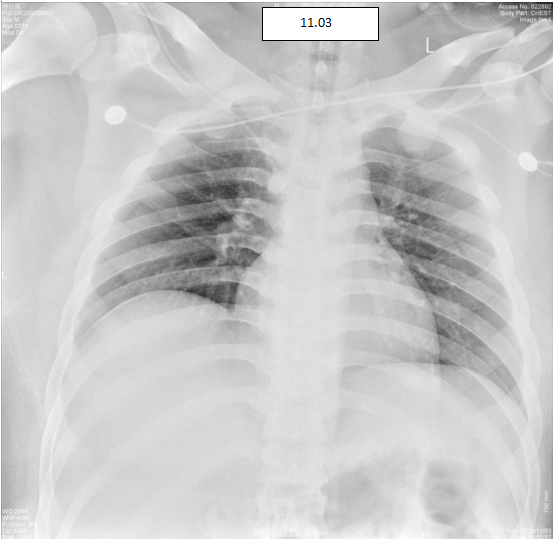

最终在莫俊德的主任医师、陈莲芳护长等医务人员的精心照料下,2周后患者氧合改善,成功脱机拔管。